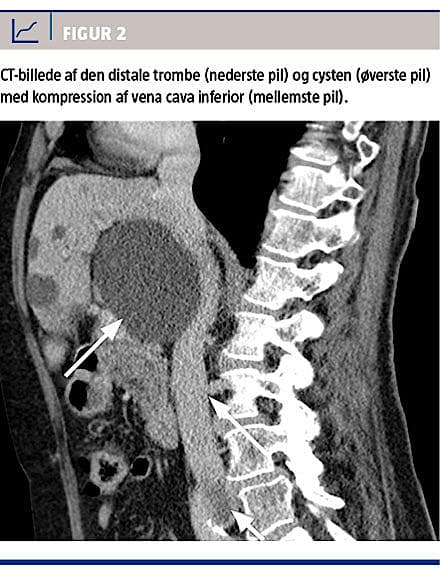

På mistanke om samtidig lungeemboli blev der udført ekkokardiografi, der ikke viste tegn til højresidig belastning. Man observerede en stor levercyste, der afklemte VCI få cm fra indmundingen til højre atrium (Figur 1).